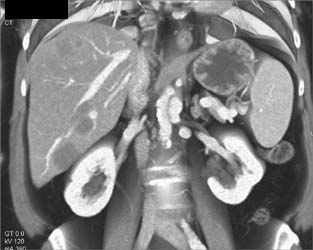

Normal Liver Venous Anatomy